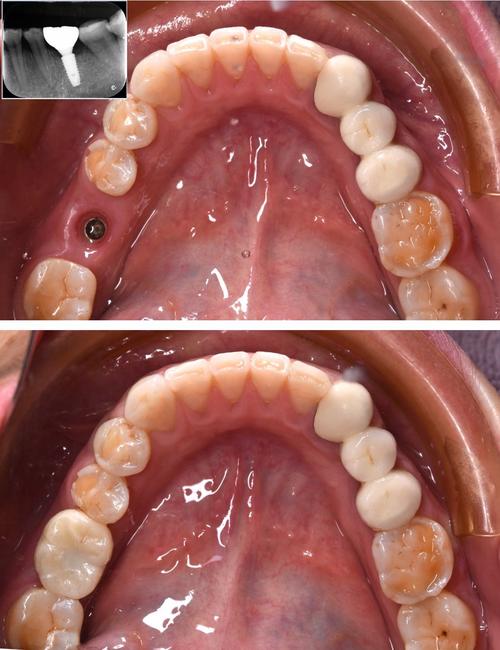

(图片来源网络,侵删)- 情况: 牙齿大部分缺失,但残留的牙根非常稳固,没有松动,没有明显炎症或感染(比如有些根管治疗后的牙齿只剩牙根,但根尖无炎症)。